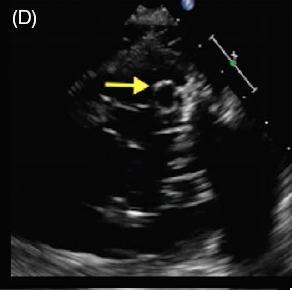

患者女,42 岁,以「急性视网膜动脉闭塞」病史就诊,既往无慢性疾病。经胸超声心动图检查发现二尖瓣后叶可见一囊状结构,可活动(图 A 和 B)。二维和实时三维经食管超声心动图检查显示一柔软的圆形结构附着于二尖瓣后叶,活动性良好(图 C ~ G)。主动脉弓、左心房、左心耳和左心室均正常。根据病变形态特征及超声表现,诊断为二尖瓣附瓣。其它影像学检查如 MRI、颈动脉多普勒超声均无异常。基于上述检查结果,考虑急性视网膜动脉闭塞为 AMVT 所致,建议外科手术切除二尖瓣附属组织,但是患者拒绝,选择随访观察。

图 G 实时三维经食管超声心动图显示一柔软的圆形结构附着于二尖瓣后叶,活动性良好